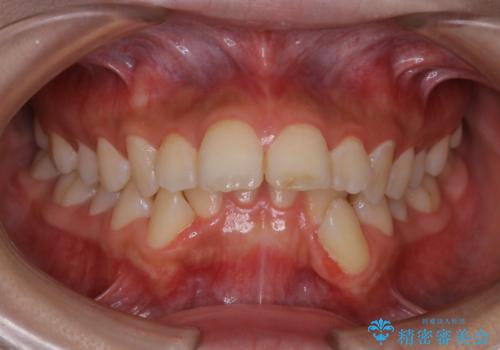

- 前歯のガタガタと前歯で食べ物が咬み切りにくいとのことで来院されました。

ガタガタの度合いが強く上下左右の前から4番目の歯を合計4本抜歯する計画としました。

また目立たない装置をご希望されたので、フルリンガルでの矯正治療となりました。